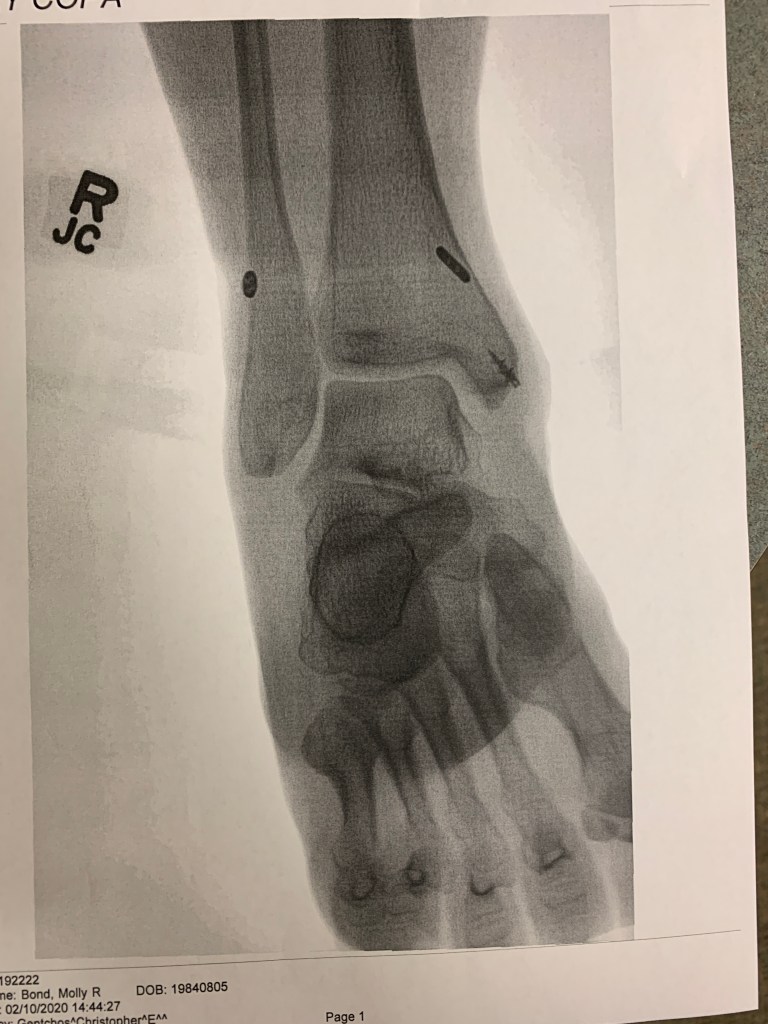

More X-rays were taken and you can see the hardware. (Picture below). It is actually pretty interesting to see the screw for the reattached ligament and the tightrope that goes through the bone.

To urgent care we went immediately. After an “oh no” from the doctor, X-rays showed that I ended up having multiple fractures in my fibula. And the suggestion that I go to an orthopedic surgeon ASAP. (Pictures is the X-rays are below)

The next day, a second opinion. This doctor was great. He calmly explained exactly what the injury was – basically when I fell I dislocated my tibia & fibula which resulted in fracturing my fibula, injuring the deltoid ligament in my ankle and possibly injuring another ligament. He drew out the injury on a white board and showed us the X-rays. Surgery was necessary to fix everything. Even though I had already been told I needed surgery it didn’t help hearing it again but I was able to hold back the tears. Hearing you need surgery is like getting punched in the gut. Your brain tries to process the information but everything becomes really cloudy and anxiety starts to set in. And before I knew it, surgery was getting scheduled for the following week and a hard cast was being put on my leg to help protect the injury.

Pictures below of X-rays

Break in my fibula

Red arrows show where everything should be placed for it to be normal